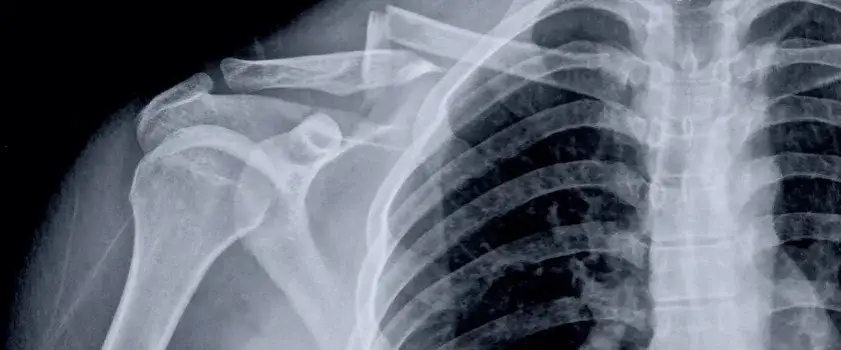

Ile trwa rehabilitacja po złamaniu obojczyka? To pytanie zadaje sobie wiele osób, które doświadczyły tego urazu. Czas rehabilitacji jest kluczowym elementem procesu zdrowienia i może się różnić w zależności od rodzaju złamania oraz zastosowanego leczenia. W przypadku prostych złamań bez przemieszczenia rehabilitacja może trwać od 3 do 6 miesięcy. Warto jednak pamiętać, że każdy przypadek jest inny i wymaga indywidualnego podejścia.

Rehabilitacja po złamaniu obojczyka to kluczowy etap w procesie zdrowienia. Czas jej trwania zależy od rodzaju złamania oraz zastosowanego leczenia. W przypadku prostych złamań, które nie wymagają operacji, rehabilitacja może trwać od 3 do 6 miesięcy. To ważne, aby pacjenci zdawali sobie sprawę, że każdy przypadek jest inny i czas rehabilitacji może się różnić w zależności od indywidualnych okoliczności.